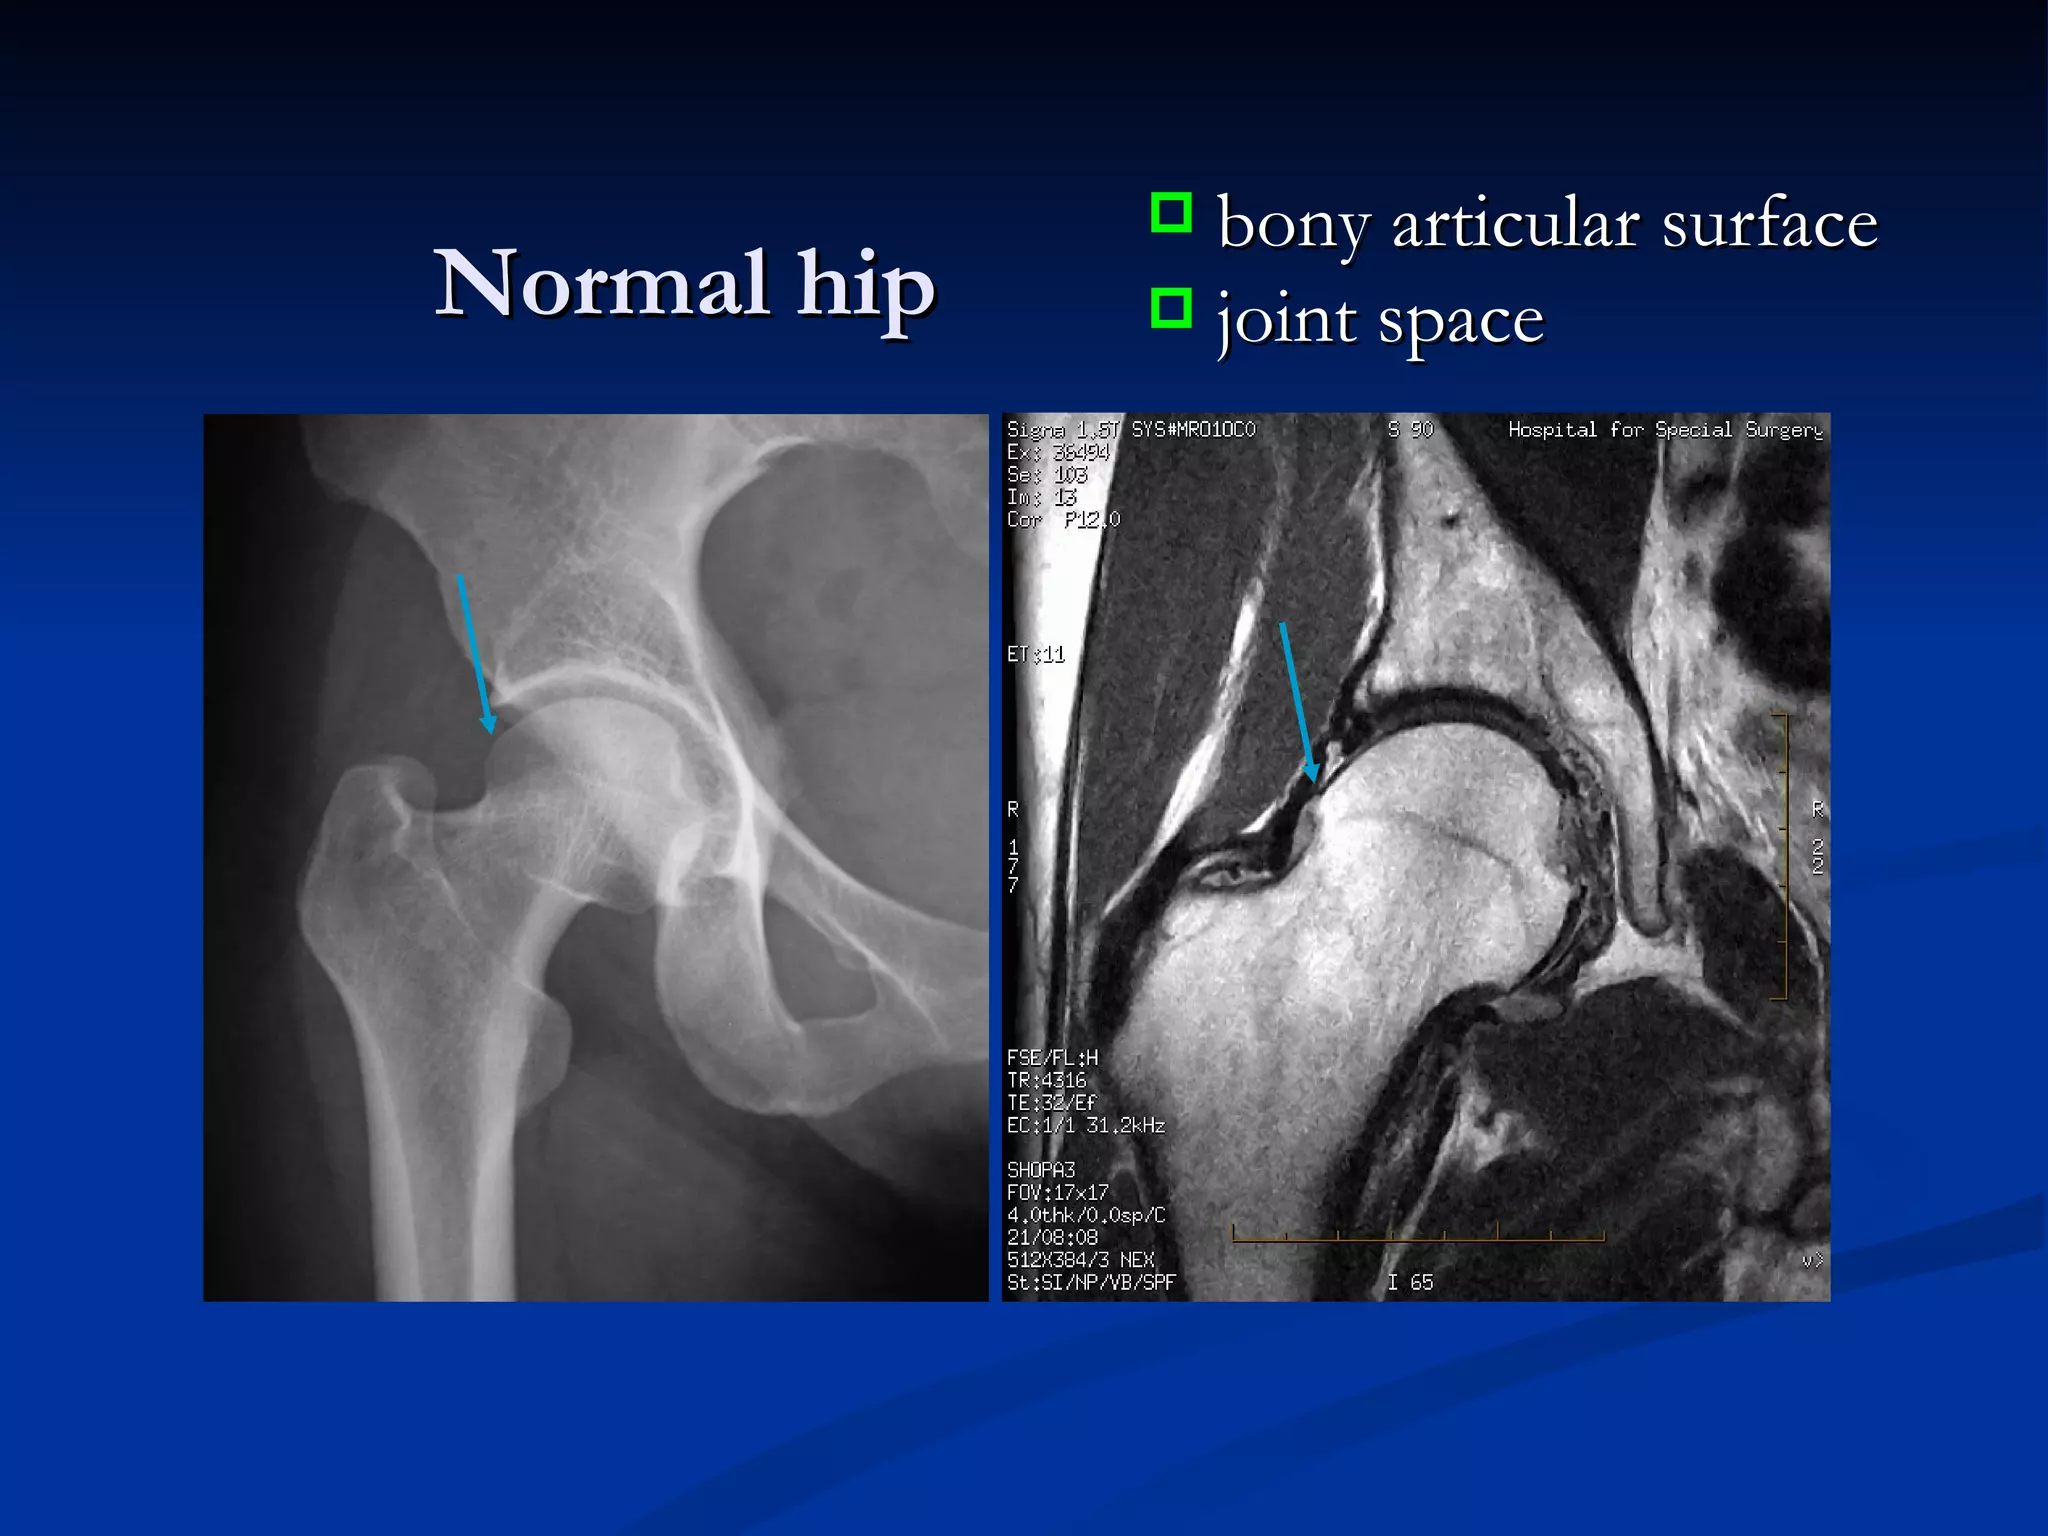

Normal hip bony articular surface joint space

Normal hip bonyarticular surface joint space